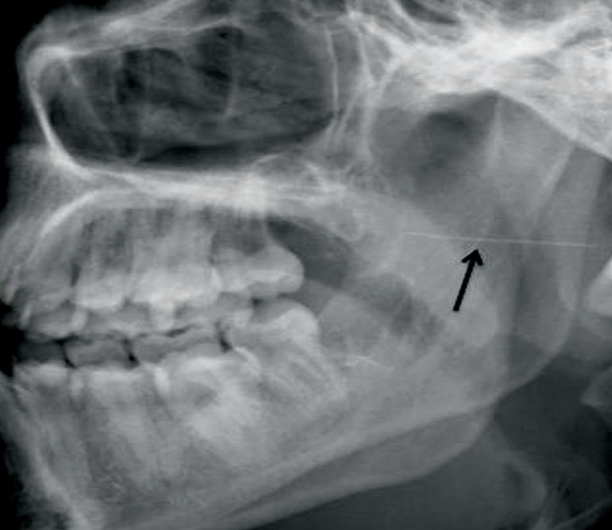

Complication – After administering an IANB, the pt's face on the side that was injected "droops" and the pt is unable to close their eyelid

Management – Most likely local anesthetic was administered into the pt's facial nerve (cranial nerve VII) which partly resides in the parotid gland. Reassure the pt that the numbness will be transitory and will wear off as the local anesthetic is metabolized. Instruct pt to manually close their eyelid and moisten with eye drops as needed until function is regained ***

Prevention: Facial Nerve Paralysis

In almost all cases, this complication is an operator error while giving the IANB (or Gow-Gates). Always contact bone before injecting! ***